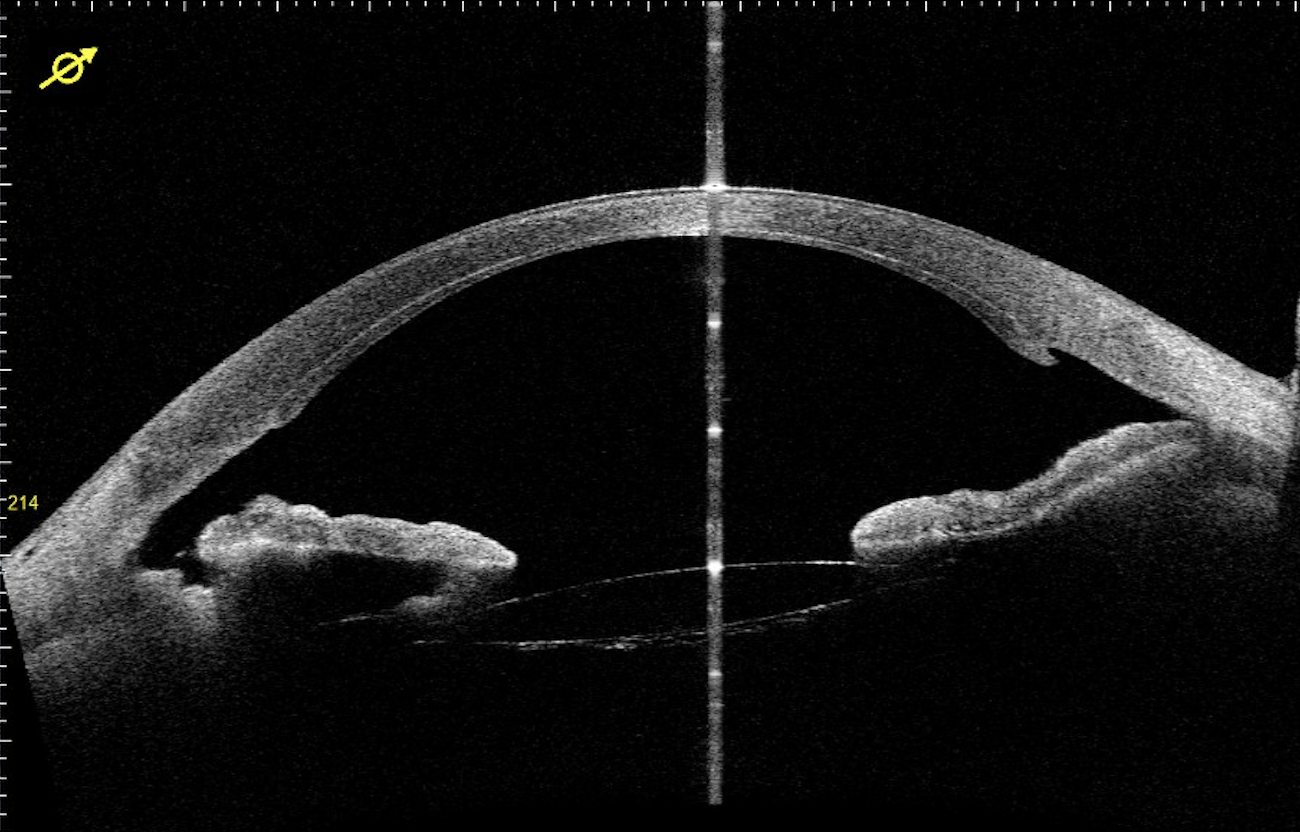

Diagnosi e trattamento del cheratocono

Una volta considerata patologia rara, il cheratocono è una deformazione ectasica della cornea ed esordisce in adolescenza. Una diagnosi nello stadio precoce, assicura una strategia terapeutica efficace e non invasiva, grazie all’introduzione del cross-linking.

Chirurgia e trapianti di cornea

La rivoluzione dei trapianti lamellari ha permesso di ridurre l’invasività dell’intervento. Patologie come la distrofia di Fuchs, cheratocono avanzato ed esiti di cheratiti infettive oggi possono essere trattate favorevolmente con le nuove tecniche.